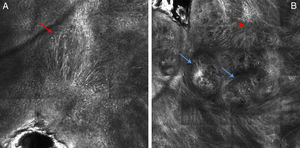

The lesion was evaluated using reflectance confocal microscopy (RCM), which showed marked destructuring of the epidermis, with irregularly shaped keratinocytes instead of the typical honeycomb or cobbled appearance, the presence of pagetoid cells with a multifocal distribution and dendritic morphology, a loss of bright rings, the absence of a defined pattern at the dermoepidermal junction, the presence of atypical cells forming junctional and dermal nests, and a dense inflammatory infiltrate with fibrosis and abundant melanophages (Fig. 2). With a suspected diagnosis of melanoma, the lesion was excised.

RCM is a noninvasive technique with a resolution very similar to conventional histology. It provides horizontal images and can be considered an intermediate diagnostic method between dermoscopy and histopathology, frequently avoiding unnecessary surgical excisions. However, the presence of cellular atypia on RCM study in these cases means that a diagnosis of melanoma cannot be ruled out. As is to be expected, abundant melanophages and collagen bundles are also observed.5